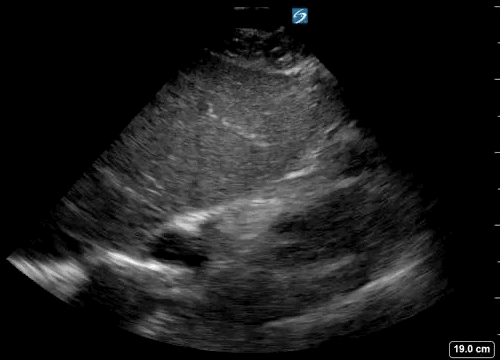

After you arrive at the unit and don PPE, the patient has just become unresponsive, ALS started with the 1st rhythm check showing pulseless electrical activity. You decide to be the dedicated performed of echo in life support (ELS). On the 2nd rhythm check the following echo loop is recorded:

Clip 1- 1st 10 sec recorded echo loop during the 2nd pulse check

• This is a subcostal/subxiphoid 4 chamber view, one of the most commonly used views in cardiac arrest.

The advantage of this view is it allows the operator to position the probe even during compressions in preparation for a pause in CPR for a rhythm/pulse check.

However, a 2021 study demonstrated superior images and shorter time to image acquisition using the parasternal long axis view. Of note this was with real patients but in simulated cardiac arrest - physiology and imaging may be different in true arrest!

• Yes, the heart can be seen to beat.

• Yes, rather than just slight ‘twitching’ of one area, there seems to be organised contratility, albeit slow and irregular.

• Challenging question

Right at the beginning of the image, there is a suggestion the RV may be dilated, and at times the RA may appear to be pushing the inter-atrial septum into the LA. These features may suggest right heart failure, most likely given the history due to PE.

However, the RV is known to dilate in cardiac arrest of any etiology and so be wary of interpreting these signs as diagnostic certainty.